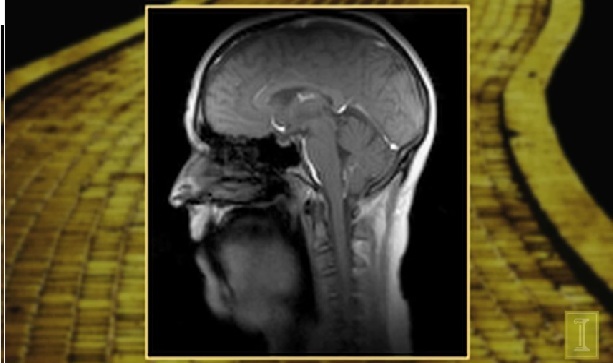

透過最新的影像技術,得以一窺口腔發聲時肌肉運動的奧秘。(photo by 貝克曼研究機構)

【台灣醒報記者張禹宣綜合報導】70歲的老先生也有可能擁有35歲的好歌喉?美國科學家又有新的突破,運用最新每秒可拍100張影像的核磁共振技術,使科學家得以一窺,人在發聲時肌肉群如何協調運作,以及人類發聲的奧秘,以方便科學家研究透過訓練,是否可能讓人類聲帶「返老還童」。

現在美國研發最新的核磁共振影像技術,可用來探究口腔部位的肌肉如何完美分工。伊利諾大學視聽科學的助理教授亞倫.強森表示,聲音僅是從兩塊薄如紗的肌肉震動產生,卻能產生千變萬化的效果,而人們認定年齡的方式通常是從聲音的萎縮、退化以及嘆息聲來評估,也對聲帶「凍齡」的醫學技術帶來啟發。

最新的核磁共振攝影技術每秒可以拍100張畫面,相較以往每秒10張的傳統共振更能捕捉人類唱歌時高速運動下的口腔肌群。因此強森表示,他將利用這些影像畫面去分析聲帶老化的過程。